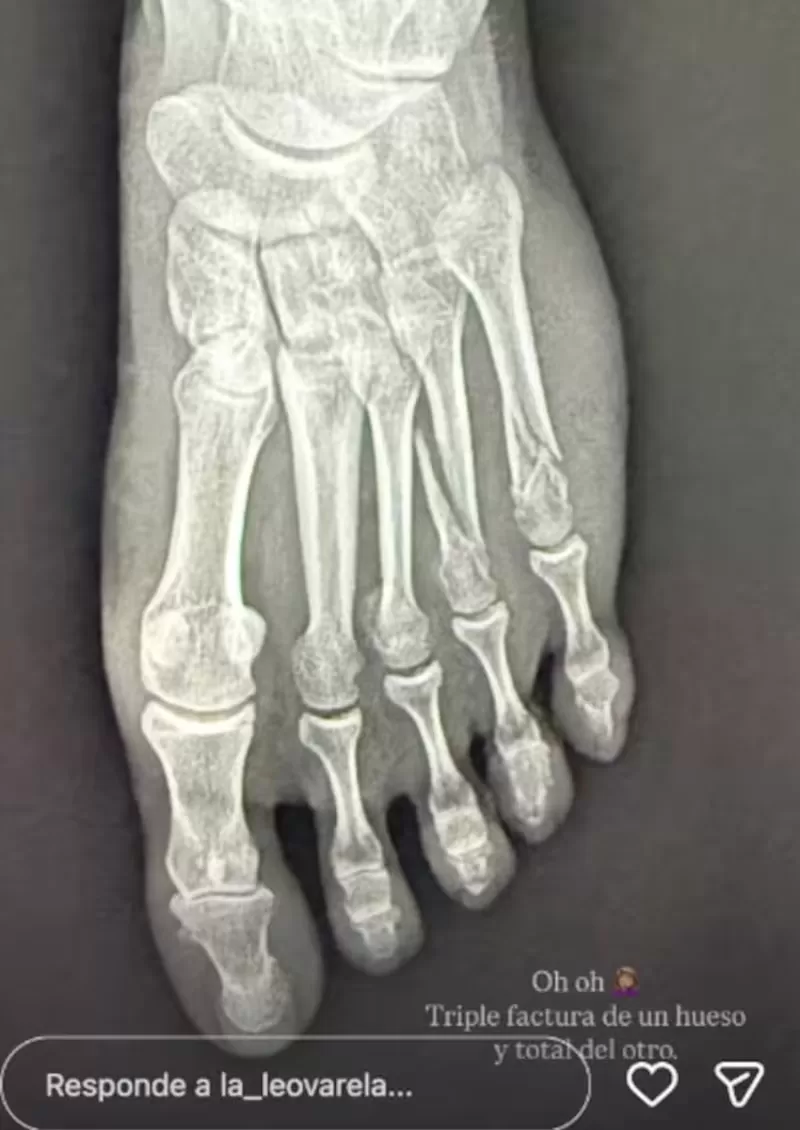

Asimismo, fue que se confirmó que sus huesos sufrieron una lesión grave. La intérprete posteó un registro de la radiografía: «oh, oh. Triple Fractura de un hueso y total del otro», escribió acompañando la fotografía.